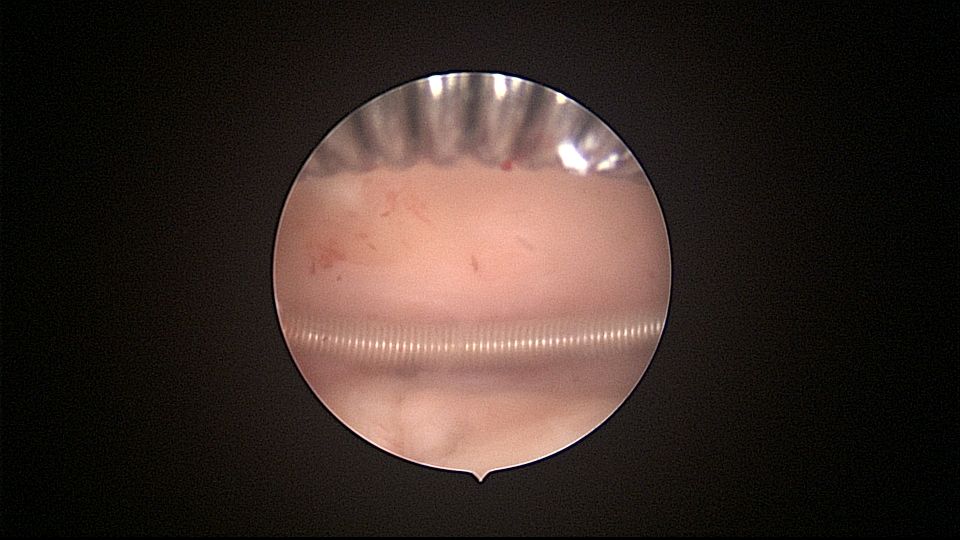

患者54岁,G1P1,顺产1次。安环33年,绝经3年,外院取环失败,子宫穿孔,盆腔积血。子宫后位,宫腔镜见宫颈管组织杂乱,宫颈管上段前壁不规则潜行假道,假道后侧寻找到宫颈内口。扩张宫颈内口,进入宫腔,见O型环位置正常,异物钳取出节育环,宫腔内看不到子宫穿孔。腹腔镜见盆腔积血约400ml,子宫前壁中段偏左见直径0.5cm不规则穿孔,少许渗血,缝合修补子宫穿孔。因左侧卵巢囊肿,患者及家属要求切除双侧附件。